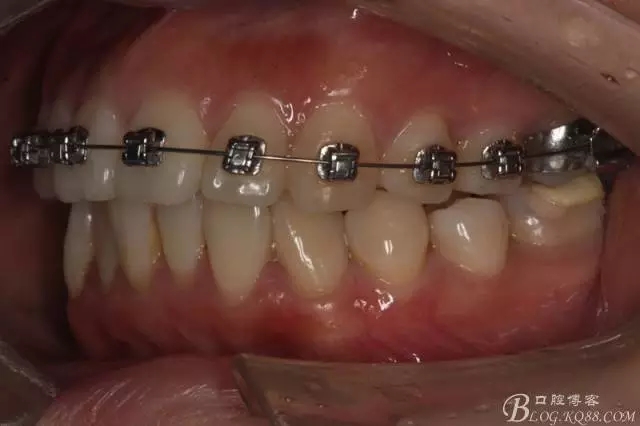

該病例主要為17、27頰側(cè)位同時伴有伸長,當然種植支抗可以解決,但還有簡單實用的辦法嗎?如圖,在橫腭桿遠中延伸出牽引鉤,位置盡量遠離合平面,7粘舌側(cè)扣,牽引力的方向為壓低及舌向,下圖為兩個月的效果,17已到位,27還未到位。